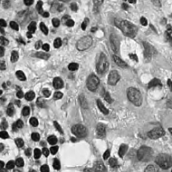

Figure 1: (a) H&E stained image; (b) H-component; (c) E-component; (d) fully annotated label; (e) Voronoi label; (f) cluster label; (g) inaccurate and incomplete area of (e) and (f), compared with (d). In (e) and (f), the green, red, and black pixels denote the label of positive, negative and ignored area, respectively. In (g), the yellow and blue masks denote the inaccurate and incomplete area, respectively.

II-A2 Hematoxylin Component Extraction

According to the principle of H&E staining [4], H-component of the original pathology image can provide sufficient information for nuclei segmentation and reduce the stain variance as well. Thus, we apply the stain separation method [49] to separate H-components and E-components from the original color images.

As shown in Fig. 1, although part of the color information is lost in the obtained H-component image, the color contrast between the nuclear and non-nuclear regions is enhanced.